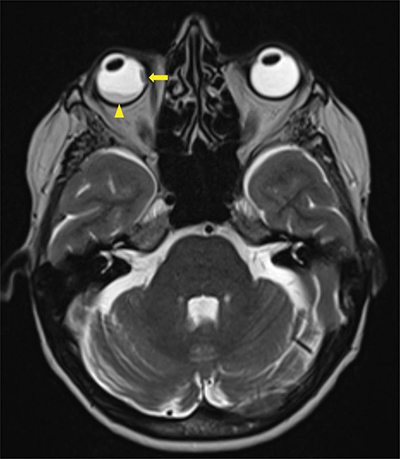

Figure 3

Axial T2 Dixon MRI-scan showing a second intra-orbital metastasis (arrow) invading all layers of the eyeball including sclera and a secondary retinal detachment (arrowhead).

A magnetic resonance image (MRI) demonstrated a 16.5 × 10.7 mm right intraorbital mass of superolateral topography invading all of the ocular globe layers (Figure 1), and a second medial 8 × 3.7 mm right intraorbital mass (arrow, Figure 2 T1, Figure 3 T2). The posterior sclera and the periorbital fat were invaded, with partial right retinal detachment (arrowhead, Figure 2 T1, Figure 3 T2).